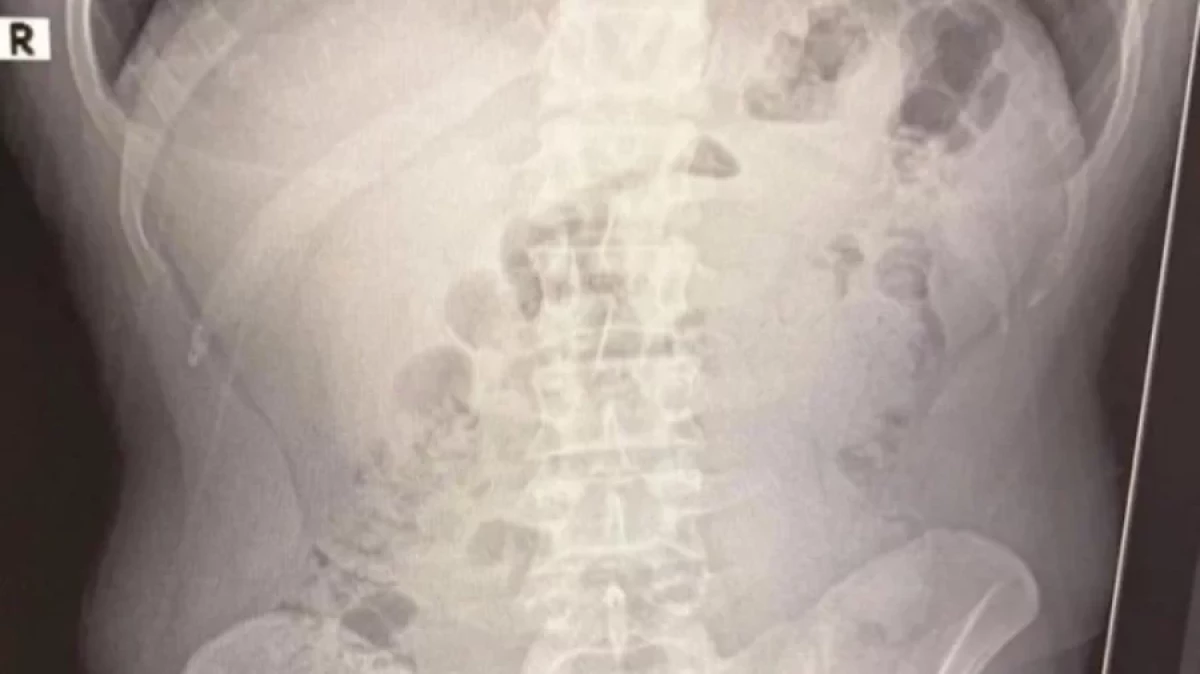

Rentgen tekshiruvi natijasida ularning oshqozonida metamfetamin kapsulalari borligi aniqlangan. Sud tomonidan Eron fuqarolarini hibsda saqlashga qaror qabul qilindi.